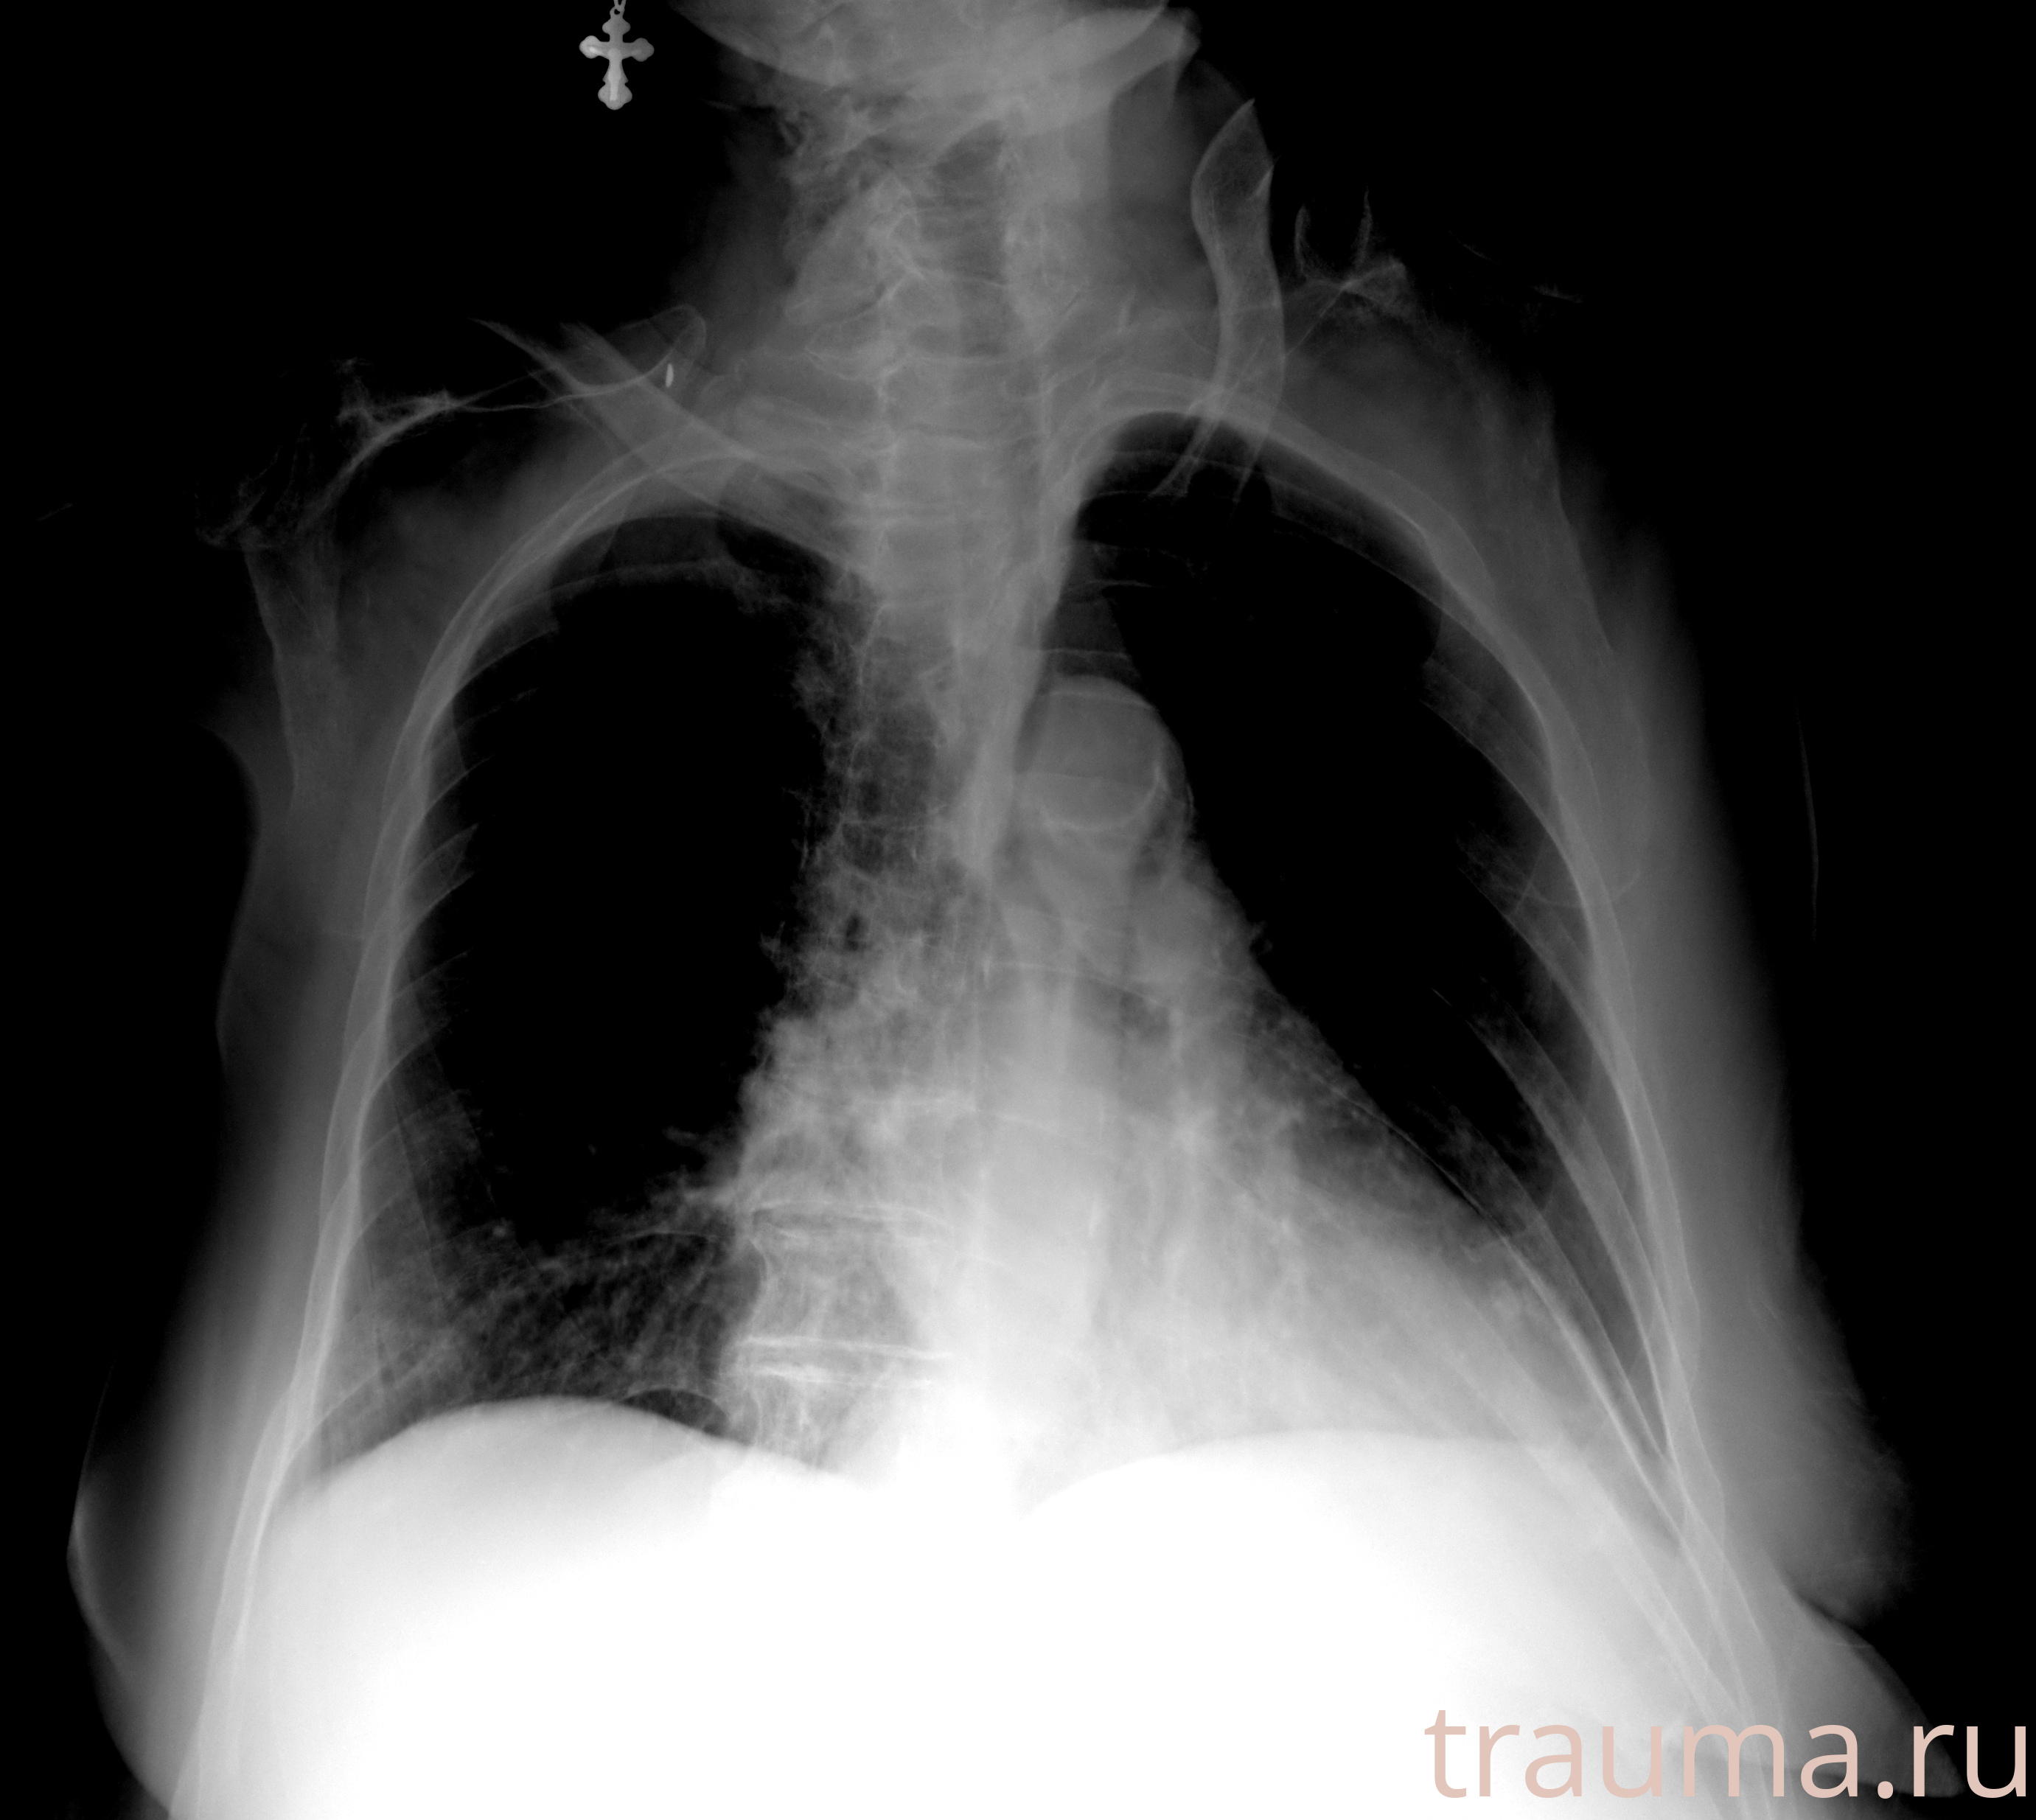

Рентген на дому: по вашему адресу приезжает врач-рентгенолог, травматолог-ортопед с мобильным рентгеновским аппаратом, проводит диагностику травмы или заболевания, делает необходимые рентгенограммы, дает рекомендации по дальнейшему лечению. Получить качественные снимки в домашних условиях возможно благодаря уникальной методике, разработанной МосРентген Центром для института  Склифосовского